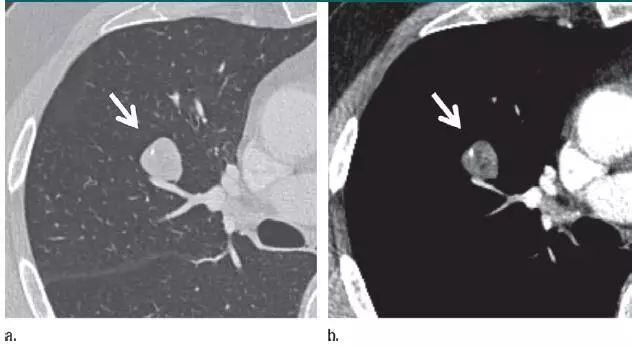

1. 错构瘤

图 1 层厚 1 mm 的 CT 横断面图像,(a)为肺窗,(b)为软组织窗,显示边缘平滑、内含脂肪和钙化的实性结节(箭头),符合错构瘤表现。不建议进一步 CT 随访。